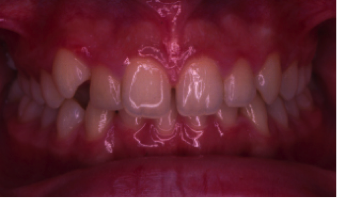

叢生(そうせい)

20歳/女性

悩み:歯がデコボコ

八重歯が押し出されて歯がでこぼこに並んでいる状態

治療期間:約2年4ヶ月

治療前

治療後

奥の歯が倒れて狭くなっている台形の歯列を広げて歯を起こす治療で、奥の歯が見えるようになるUの字型に治しました。

上の歯下の歯、それぞれ2本づつ第一小臼歯を抜歯した治療となりました。

歯を見せて笑えるようになり喜んでもらいました。